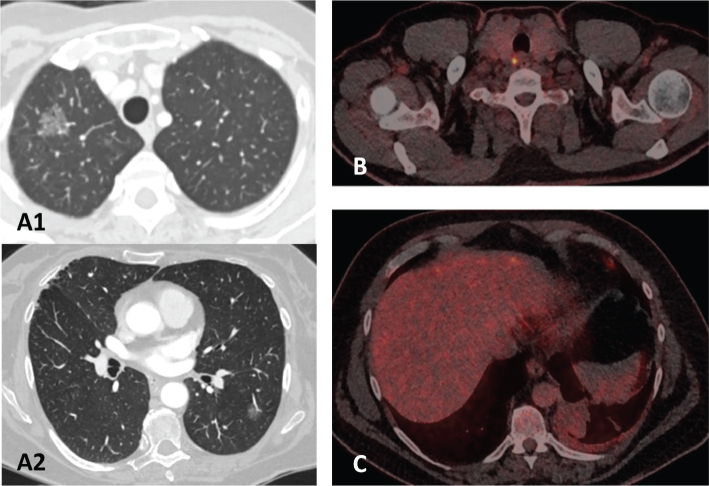

背景:多学科团队(MDT)会议是肺癌治疗的金标准。最近的一项研究发现,基于虚构病例的丹麦肺癌MDTs在分期和治疗建议方面存在差异。本简短报告介绍了一次全国肺癌MDT会议的结果,该会议重新评估了这些疑难病例。方法:对来自丹麦肿瘤学、肺病学、放射学、核医学和胸外科的52名肺癌专家对15例疑难病例进行再评估。参与者与他们通常的MDT同事一起分组。病例在全体会议上提交,参与者讨论病例分期、治疗意图和治疗方案,就像他们在与同事进行常规MDT时一样。如果各个MDT小组之间出现分歧,则在全体会议上进一步讨论该案件。描述性统计用于评估一致性。结果:3例(20%)患者在肿瘤淋巴结转移(TNM)分期、治疗意向和推荐治疗方案上完全一致。10例(67%)达到分期一致。关于分期的差异源于对多灶性肺癌与同步性肺癌、淋巴结受累程度和胸膜液恶性状态的争论。治疗建议的差异主要是由于对性能状况的信息不足。解释:在国家全体会议上讨论复杂病例时,丹麦肺癌MDTs的分期和治疗意图差异大大减少。然而,对于困难的肺癌病例,MDT推荐不同的治疗方法,这突出了为选定的一组肺癌患者召开全国MDT会议的必要性。

Results: Complete agreement on tumor node metastasis (TNM) staging, treatment intent, and recommended treatment was reached in three cases (20%). Agreement on stage was reached in 10 cases (67%). Discrepancies regarding stage arose from debates regarding multifocal versus synchronous lung cancers, degree of lymph node involvement and the malignancy status of pleural fluid. Differences in treatment recommendations were mainly due to insufficient information about performance status.